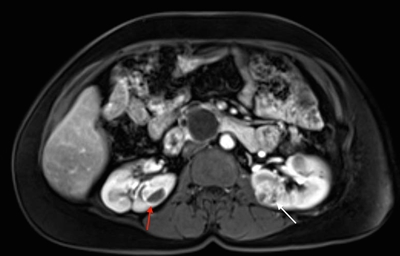

More than 55% of individuals with von Hippel-Lindau disease (VHL) only develop multiple renal cell cysts. VHL-associated renal cell carcinomas (RCCs) are characteristically multifocal and bilateral. These RCCs present as masses with both cystic and solid characteristics.[1] In VHL, the cumulative risk of RCC was reported to be 24% to 45%. RCCs smaller than 3 cm tend to be low-grade (Fuhrman nuclear grade 2) and minimally invasive.[2] However, their growth rate varies widely.[3] An investigation of 228 renal lesions in 28 patients who were followed for at least 1 year showed that transition from a simple cyst to a solid lesion was infrequent.[1] Complex cystic and solid lesions contained neoplastic tissue that was uniformly enlarged. These data may be used to predict the progression of renal lesions (from benign to malignant) in patients with VHL. Figure 1 depicts bilateral renal tumors in a patient with VHL.

Figure 1. von Hippel-Lindau disease–associated renal cell cancers are characteristically multifocal and bilateral and present as combined cystic and solid masses. The red arrow shows a lesion with a solid and cystic component, and the white arrow shows a predominantly solid lesion.